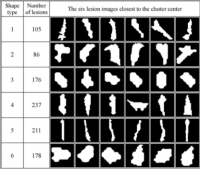

Interdisciplinary Master thesis in the domain of "Characterization of Cerebral Small Vessel Disease-Biomarkers in a Clinical Cohort"

Neurodegenerative diseases such as Alzheimer’s Disease commonly coexist with cerebrovascular diseases in older people. Cerebral small vessel disease (SVD), the most common vascular cause of dementia, is characterized by specific imaging biomarkers in conventional MR scans. Thanks to automated methods, segmentation masks of these imaging biomarkers can be obtained in large numbers with minimal time needed. In this thesis, a variety of different high-level characteristics shall be extracted from the segmented/detected biomarkers of CSVD and potential subtypes/phenotypes and relations identified and analysed. The effort will be part of the collaboration between the “MedDigit” (Medicine and Digitalization) group and the “Mixed cerebral pathologies and cognitive aging” research group, a multidisciplinary team with profound expertise in both the technical as well as the medical aspects of this thesis.